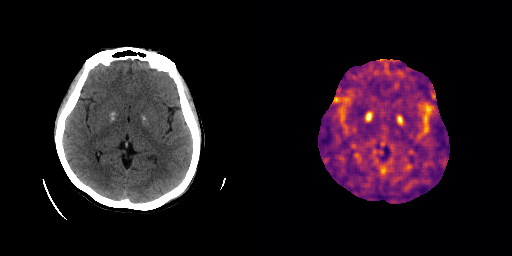

fig:qualitative_ich

ICH

healthy

We show some slices with examples of ICH in \figurereffig:qualitative_ich as well as surface renderings of scans of subjects with cranial fractures in \figurereffig:qualitative_fractures. (As a reference we also included the same examples for the AE in Appendix D in \figurereffig:qualitative_ich_ae.) It is noticeable that the reconstruction error is high where there is an anomaly. The reconstruction error generally seems to continuously depend on the amount of the patch that is anomalous, as the error maps generally seem to be rather smooth.

The performance for the models used for \figurereffig:qualitative_ich and LABEL:fig:qualitative_fractures are shown in \figurereffig:roc_performance. We observe see that the detection of fractures is the more challenging task for our method than the detection of ICH. This might be due to the smaller number of scans available to evaluate it on (see Appendix B). To put these results in context we provided a table with the inter rater agreement on these tasks in Appendix B: The performance in terms of AUROC is around lower than the average raters.